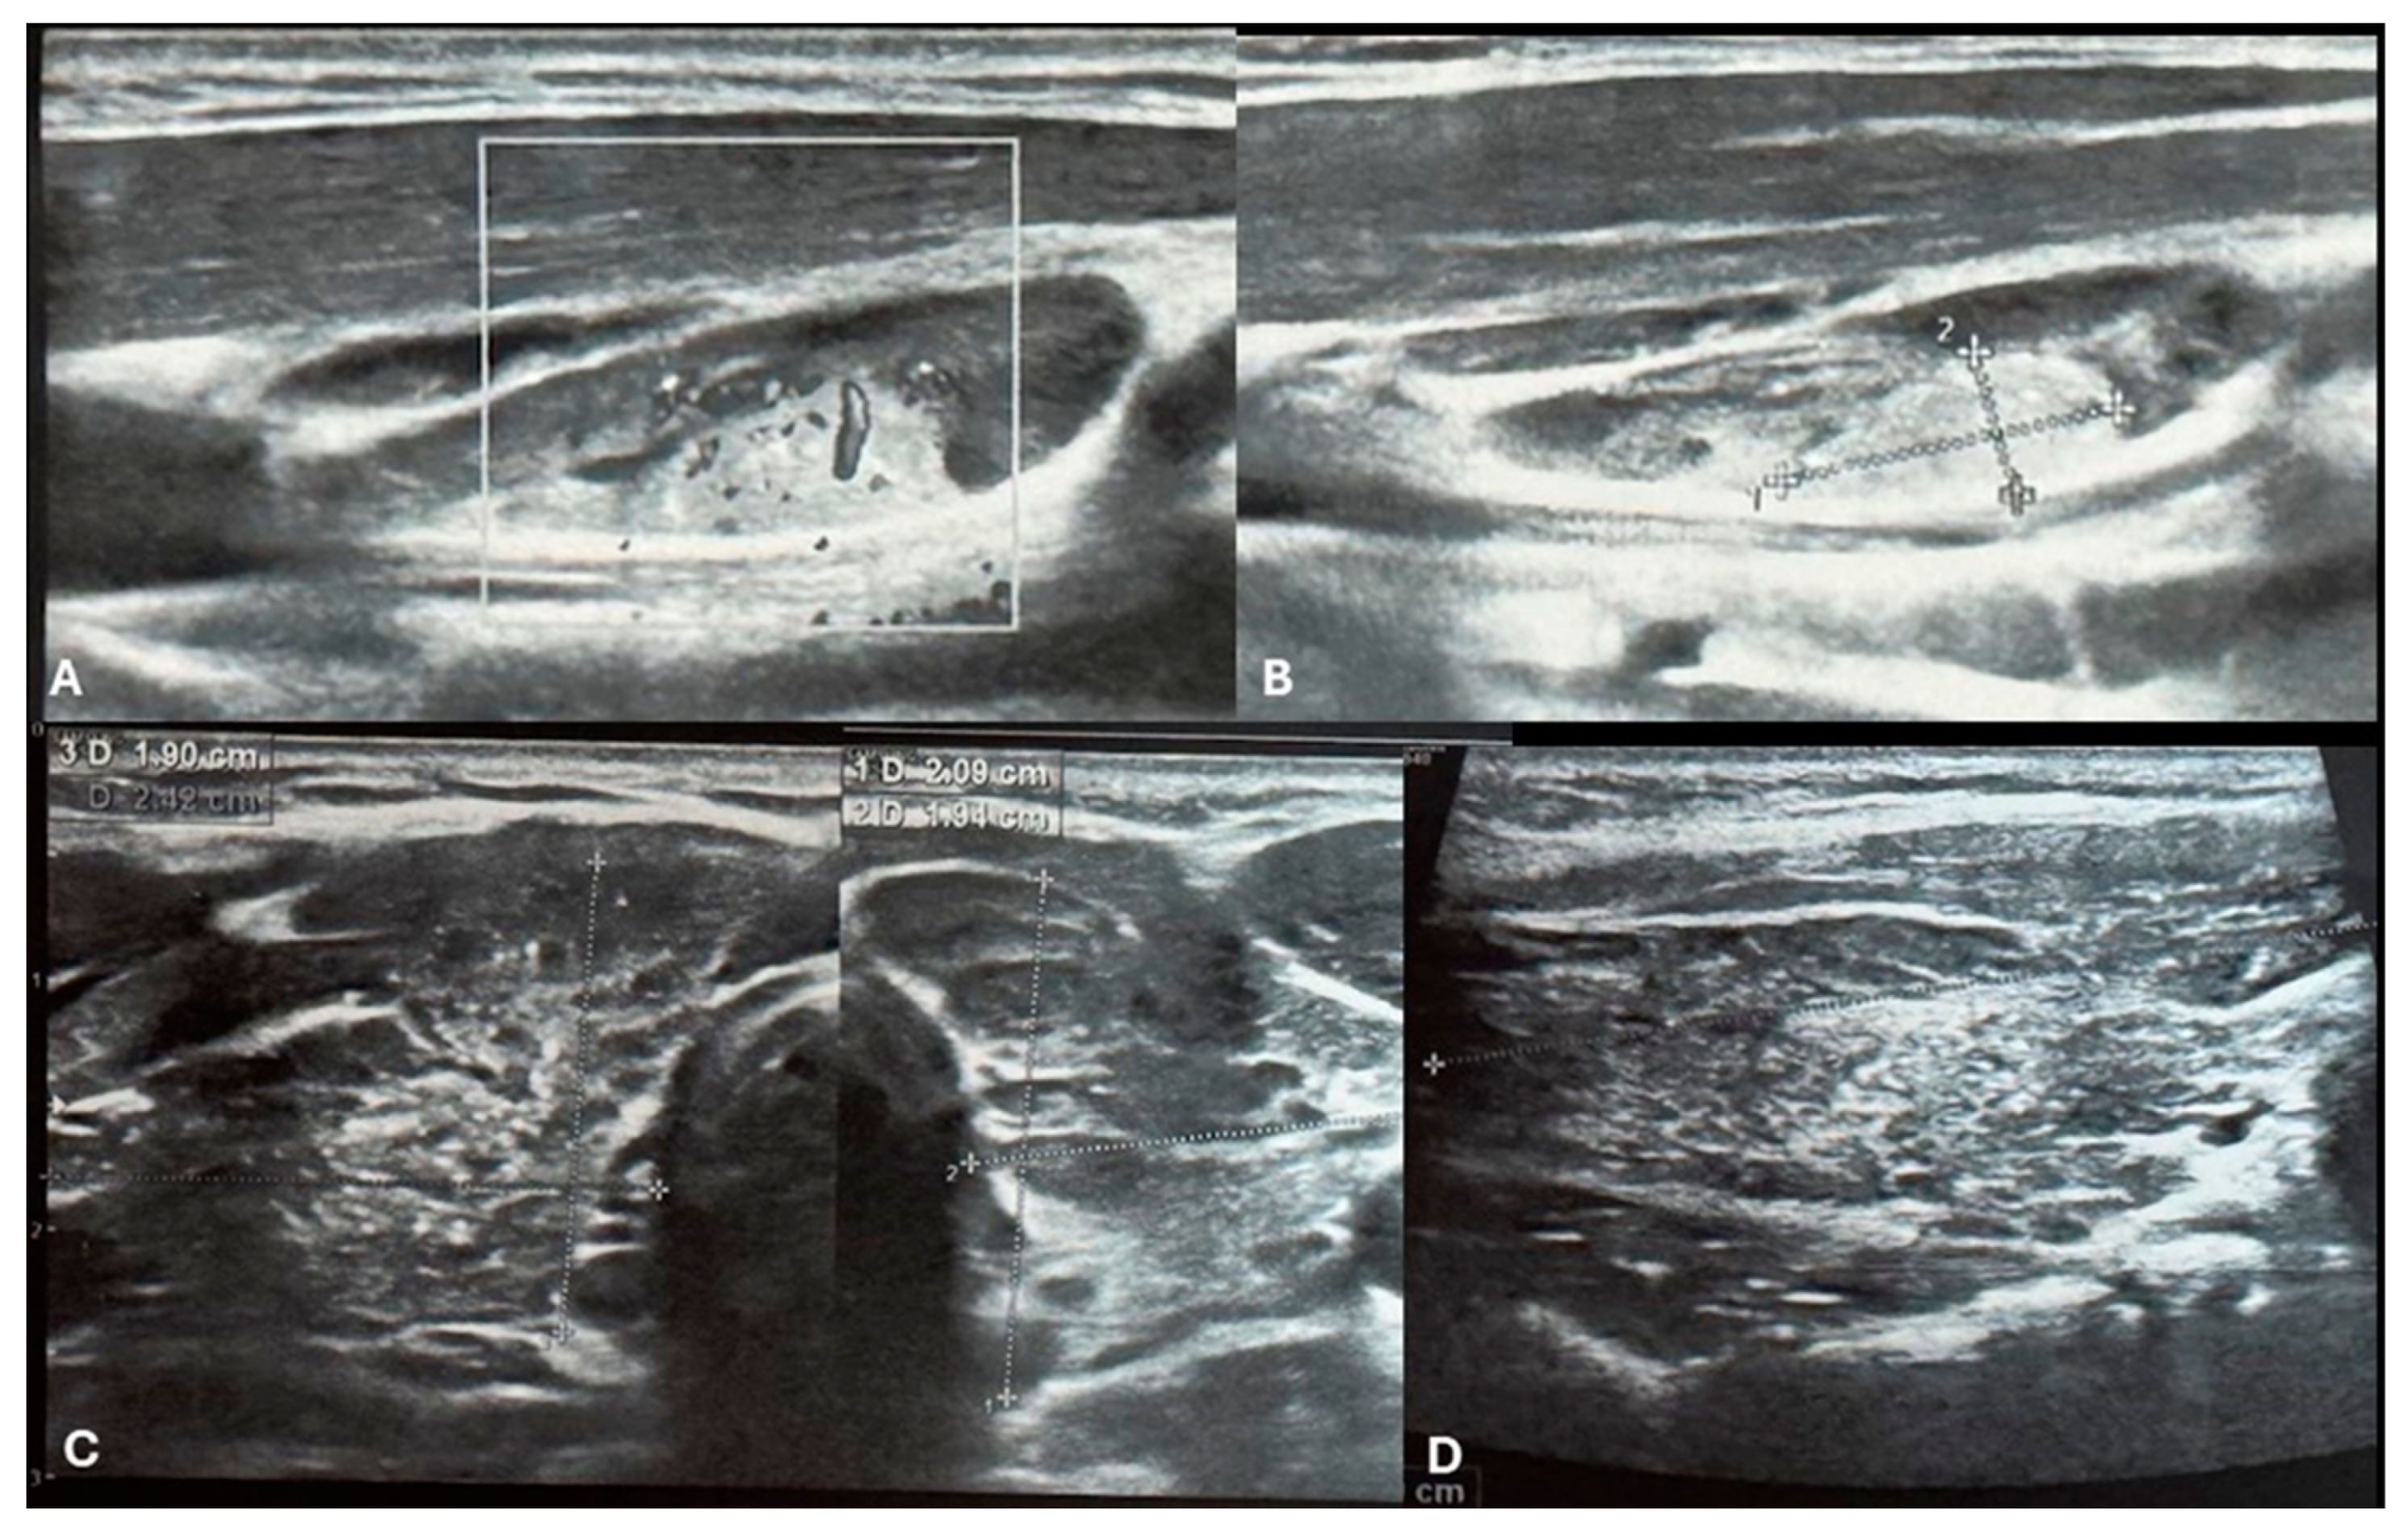

Figure 1. Ultrasound imaging of the thyroid and neck region. [A, B] Ultrasound images depict a vascularized hyperechoic lesion measuring 1.01 x 0.45 cm located within a lymph node in the upper cervical level. This finding raises suspicion for malignancy due to pathological vascularization and its proximity to the right thyroid lobe. [C] Transversal images of right and left lobe showing remodeled thyroid gland as a result of autoimmune thyroiditis. The thyroid parenchyma demonstrates characteristic heterogeneity, consistent with the chronic inflammatory changes seen in AIT. Additionally, multiple small microcalcifications are visible throughout the right thyroid lobe [C&D].

Repeat ultrasonography revealed multiple small microcalcifications scattered throughout the right thyroid lobe and a suspicious lymph node adjacent to the right thyroid lobe. The lymph node exhibited a hyperechogenic lesion with pathological vascularization, raising concern for malignancy [Figure 1.A,B]. Fine-needle aspiration biopsy (FNAB) of the right thyroid lobe was performed, revealing cytological findings of dispersed groups and sheets of thyrocytes with nuclear enlargement, clearing, occasional intranuclear grooves, and focal oxyphilic metaplasia. The background contained numerous lymphocytes, scattered multinucleated giant cells, colloid, and blood. These findings were classified as Bethesda category III (atypia of undetermined significance, AUS) with concurrent features of chronic lymphocytic thyroiditis.